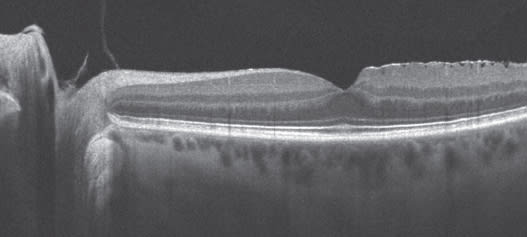

Vitreomacular traction syndrome can be difficult even for a retina specialist to diagnose without SD-OCT. Let's say a patient has reduced vision and a moderate cataract, but the vision seems to be just a little bit worse than the cataract surgeon would expect it to be. There is no macular degeneration, no macular hole and no macular pucker. There might be a subtle reddish-yellowish change in the fovea. You scratch your head and say what's going on with this patient? With Cirrus HD-OCT, it is obviously vitreomacular traction syndrome (Figure 2). You may also have a patient who appears to have dry macular degeneration, but if SD-OCT shows fluid and the patient is not diabetic, almost always the patient has an occult choroidal neovascular membrane that needs to be addressed before the cataract is removed.

Figure 2. Vitreomacular traction syndrome can be especially difficult to diagnose without SD-OCT.